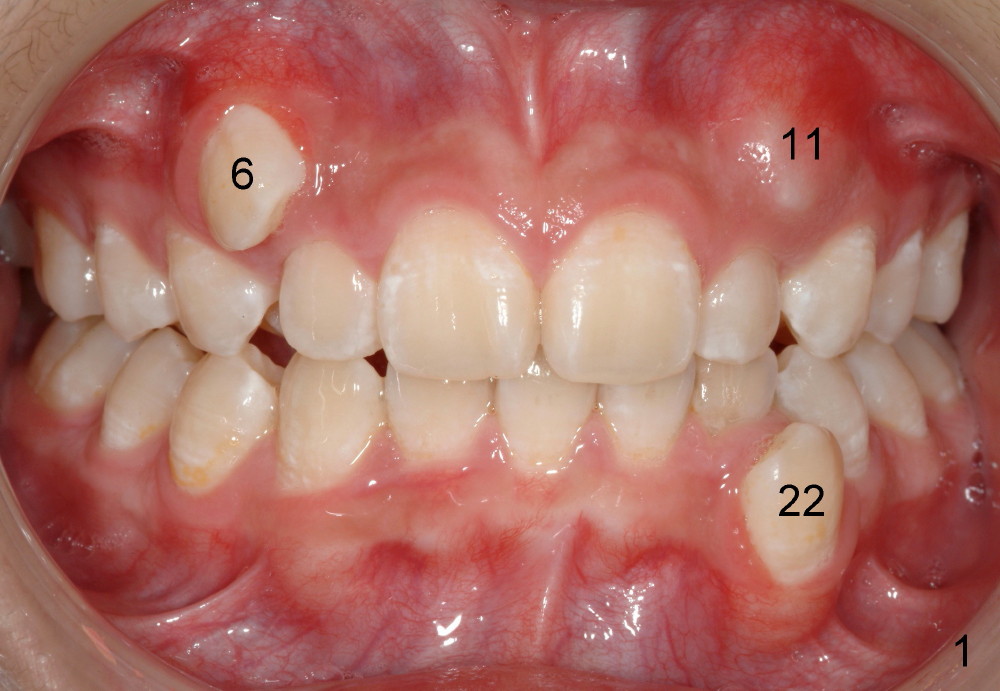

Please extract 5 and 12 in the maxilla, AND #22 in the mandible.  Yes, that is correct.  For a variety of reasons I am choosing to remove this tooth, i.e., mechanical advantage, less risk of bite opening, etc.  I also gave thought to extraction of #23 instead of #22 but the root length also points to the canine for extraction.  Bottom line, nothing made me NOT willing to extract #22, under these special circumstances.  Call me if you would like to discuss.

Tim: Thank you so much for the tip.  It appears that an alastik is placed between #6 bracket and the upper AW.  Can you recommend surgical exposure of #11?

We are teasing tooth #6 down initially with a light elastic force. This will minimize any reciprocal forces on the anterior teeth. I do not want to intrude the incisors while extruding 6. That would potentially open the bite.

You will see tooth #11 continue to erupt spontaneously. In the initial photos, it was not visible. It was simply mechanically blocked out. And the tissue will b the best when the tooth erupts spontaneously. Bet on 11 to erupt😉 and a couple more mm of eruption and I will b able to place a button and like 6, begin to tease down faster.

I hated to extract his lower left canine, more due to expected difficulty.  Amazingly, the patient was more ready for extraction than me.  He said that the tooth was not of use at all.  He has been under my care periodically for a while.  Her mom did not want to have treatment for his deciduous teeth.  Besides, he is my daughter's classmate.